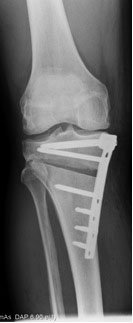

After making the cut with a saw, gradually open up the gap in the bone by using a series of fine chisels. The photograph on the left shows the stepwise insertion of chisels, allowing the cut bone to be wedged open by an exact amount. The X-ray on the right shows that the tibia bone has been cut and wedged open (the wedged-open space shows up dark against the paler surrounding bone). The plate holds the wedge open. So this is a high tibial osteotomy with the opening-wedge technique.

Thus the bone is broken at the front and the back, but we try not to go right the way across. If the bone is broken right across, we have a very useful golden screw technique to line everything up perfectly. In the X-ray you can see a dark line just to the left of that slightly longer third screw from the top just below the osteotomy - this is a fracture where the chisels have broken through. That used to be a major problem with previous surgical techniques but now that slightly longer screw can be used as a reduction screw to pull the bone back into position again.

Once the gap is opened to the position that you want then put the spreaders in and undo the double chisel device and you have just got then a set of spreaders at the back of the osteotomy and you can put your plate on then and there is nothing in the way. We leave the spreaders in position until the osteotomy plate is securely fixed to the bone.The image above on the right is of an opening wedge high tibial osteotomy and is reproduced with permission of Synthes.